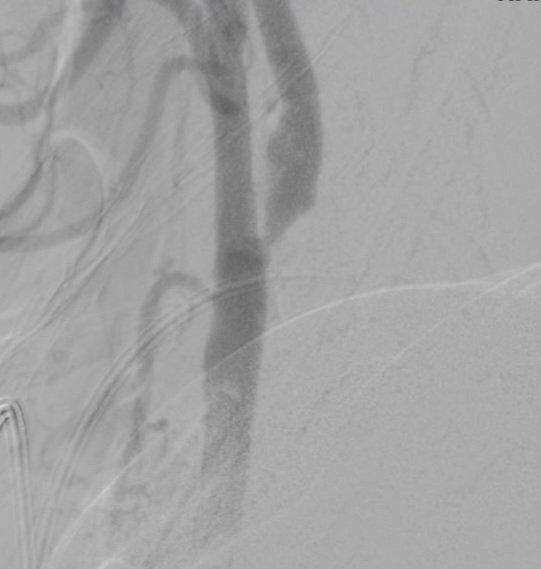

همه در یک بیمار. کاروتید راست:دایسکشن کاروتید چپ: تنگی شدید ورتبرال چپ: بسته شدن کامل از ابتدای شریان ورتبرال راست: دایسکشن و آنوریسم. درمان: استنت کویل در ورتبرال راست و نیز استنت کاروتید چپ. ادامه درمان با ضد پلاکت.